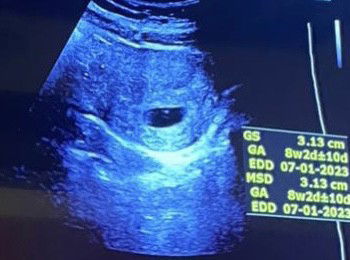

Hi semua, mengikut kiraan melalui apps, saya sudah 7 minggu pregnant. Saya buat confirmation scan pregnancy harini dan details di ultrasound menunjukkan kandungan dah 8w2d, tapi tak kelihatan janin lagi. Kiraan minggu yg mana saya perlu ikut ya? Dan normal ke 7/8 weeks belum nampak janin & heartbeat lagi? #firstbaby #firsttimemum